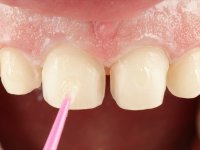

Realizado o diagnóstico e tomada a decisão quanto ao tratamento a executar, tornou-se importante definir qual a sequência de trabalho a adotar no sentido de conseguir a reabilitação da D.V.O. (V.D.O), de forma progressiva e equilibrada. Na primeira fase fez-se uma pré-impressão da arcada inferior com silicone tipo “putty” e em seguida realizou-se o preparo dentário de todo o sector posterior. O preparo para os overlays foi feito coronalmente à linha amelo cementaria no sentido de ser o mais conservador possível. A impressão foi feita com técnica de dupla mistura após afastamento gengival realizado com pasta de caulino. A provisória foi realizada com resina composta de polimerização dual. Em laboratório foram realizados os overlays após se ter aberto ligeiramente (1,5mm) a D.V.O. nos modelos montados em articulador semi-ajustável. Simultaneamente o sector antero-inferior foi encerado no sentido de acompanhar este aumento da D.V.O. Também foi confecionada uma chave de silicone translucido para posterior confeção dos provisórios antero-inferiores. Em boca foi primeiro realizada a provisionalização dos dentes anteriores utilizando resina composta previamente aquecida após preparação das superfícies dentárias para a adesão. Foi colocado o dique de borracha para promover o isolamento absoluto e posteriormente foram colados os overlays. Em laboratório foi realizada nova chave de silicone para confecionar os provisórios antero-superiores. Seguidamente em boca foram preparados os seis dentes antero-superiores após colocação do fio de afastamento gengival. Feita a preparação adequada das superfícies dentárias foi realizada a impressão com técnica de dupla mistura e a respetiva provisória. Em laboratório foram confecionadas 6 facetas feldespáticas num modelo de trabalho tipo “Geller”. A provisória foi removida e as facetas foram coladas em boca utilizando um isolamento relativo competente. Esta opção foi tomada em virtude de uma prévia experiencia negativa com a colocação do dique de borracha na mandibula. Após a colagem dos laminados antero-superiores foram dadas 12 semanas para avaliar a adaptação do paciente à nova situação e então iniciar a confeção das facetas antero-inferiores. Após colocação do fio de afastamento gengival. foram feitos os preparos dentários adequados e em seguida foi feita a impressão. Também foi feita a preparação do dente 3.4 que, entretanto, tinha sofrido uma fratura do overlay. As facetas e a restauração do 3.4 foram realizadas num modelo de trabalho tipo “Geller”. Após remoção da provisória, as facetas foram coladas em boca, utilizando um isolamento relativo pelas razões apontadas anteriormente. Após colocação do trabalho o paciente foi reabilitado por outros colegas com um implante na zona do 2.6 e substituição da coroa aparafusada sobre o implante colocado no local do 3.5. Posteriormente surgiram fraturas nos overlays dos dentes 4.7 e 3.7 que foram reabilitados com overlays em Zr.